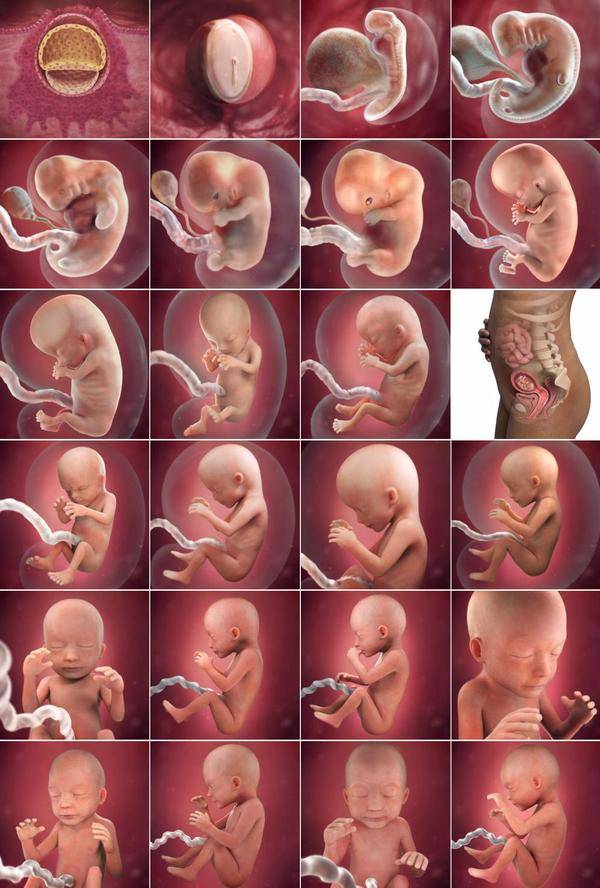

Фотография Плода В Животе

Фотография Плода В Животе 113 фотографий